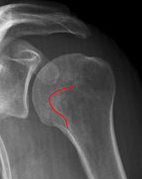

Schulter seitlich (Y-View)

Bei Luxation zusätzlich zur glenoidtangentialen Aufnahme problemlos durchführbar! Axiale Aufnahme schmerzbedingt meist nicht möglich.

- Skapula bildet sich als Y ab

- Humeruskopf projiziert sich in das Glenoid? Luxation? Luxationsrichtung?

- Weite des subacromialen Raumes exakt nur in der 10 – 15° nach kaudal angulierten Aufnahme bestimmbar („Morrison, Outlet View“)! Normalerweise 1 - 1,5 cm, < 6 mm -> wohl pathologisch, Impingment wahrscheinlich

- Normvarianten: Os glenoidale (akzessorischer Ossikel kaudal des Glenoids), persistierende Akromion- oder Korakoidapophyse, entwicklungsbedingte Pfannenranddefekte

- Schulterluxationen:

- Anteriore Luxation (2) 95%= anteriore infraglenoidale Luxation, Kopf liegt vor Glenoid

- Posteriore Luxation (2) 3%: wird häufig übersehen! Kopf liegt hinter Glenoid, Hochstand des Humeruskopfes, fixierte Innenrotation des Humeruskopfes => atypische Projektion des Humeruskopfes: “ drumstick or bulb appearance“ (Birnenform), Muldenzeichen („trough line“), „rim sign“ in der ap bzw. glenoidtagentialen Aufnahme.

Zweite Ebene, z.B. transskapuläre Aufnahme zeigt die Richtung der Luxation. Cave. rein klinische Diagnose!

- Begleitverletzungen? (-> heute umfassend mit CT/MRT zu beurteilen)

- Tuberculum majus (15%)

- Pfannenrand

- Hill- Sachs Läsion = Dorsokraniale Humeruskopf-Impressionsfraktur (50%) (Aufnahme der 1. Wahl: Stryker oder CT)

- umgekehrte Hill-Sachs Läsion = anteromediale Impression nach hinterer Luxation

- Bankart-Läsion: Abriss des vorderen Labrum-Kapsel-Komplexes bzw. Abrissfraktur des vorderen unteren Glenoidrandes (-> CT-Athrographie, Arthro-MRT)